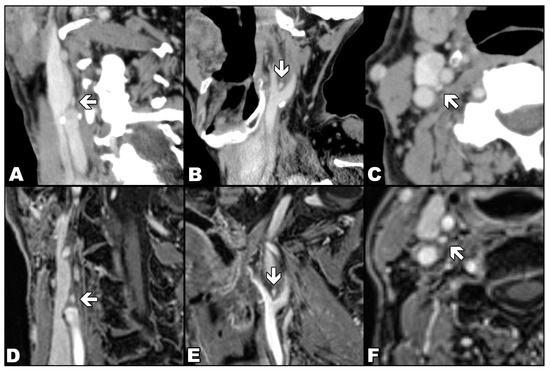

As in previous studies [7,9], CB was defined as a reproducible, ovoid, avidly enhancing structure at the inferomedial aspect of the carotid bifurcation (Figure 2). In the case of MR readings, each researcher used a semi-quantitative confidence scale from 1 to 6 points, representing the number of typical features displayed by the assessed CB and, therefore, the probability that the detected focus represents a CB. The typical features were: location adjacent to the carotid bifurcation, clearly separated oval or flame-shaped structures, transverse axis from 2 to 4 mm and longitudinal axis up to 8 mm, marked enhancement after CA, but lesser than arterial lumen. One point was assigned if no CB was visible, and six points if a single structure with all typical features of CB was detected (Table 1). A detailed assessment protocol is available in Supplementary Materials File S1.

Figure 2.

Comparison of the appearance of the carotid body (arrows) in contrast-enhanced computed tomography (upper row) with the appearance in contrasted-enhanced VIBE sequence in T1-weighted image with Dixon technique in the water-only images (lower row). Computed tomography (images (A–C)) and magnetic resonance (images (D–E)) examinations show the carotid body in three orthogonal planes: oblique coronal (A,D), oblique sagittal (B,E) and axial (C,F).